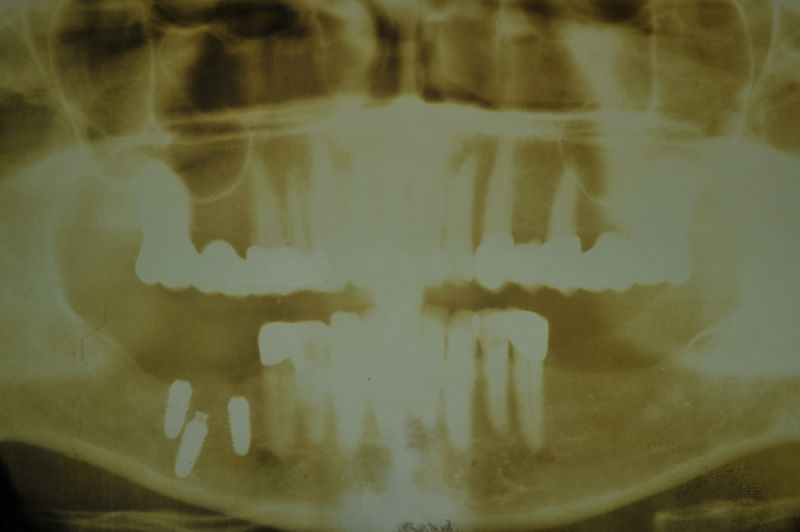

Mit dem heutigen Tag geht eine der technisch schwierigsten und anspruchsvollsten Arbeiten zu Ende, die im CMD-CENTRUM-KIEL jemals erstellt worden ist. Dabei sind es nur 10 Kronen, die benötigt werden, um die starken Kopf- und Gesichtsschmerzen der Patienten zu beseitigen.

1. Notwendigkeit einer implantatgestützten Kronenversorgung mit der Vorgeschichte, dass die Patientin eine Vielzahl von Behandlern aufgesucht hatte, die eine Implantation im Unterkiefer als nicht durchführbar einschätzten.

2. Extrem schlechte knöcherne Verhältnisse im Unterkieferseitenzahnbereich, die sich intraoperativ noch einmal als ungünstiger darstellten, als bereits in den Voruntersuchungen erkennbar.

3. Sehr dünne Implantate, die von ursprünglich zwei je Kieferhälfte auf letztendlich drei je Kieferhälfte umgeplant werden mussten.